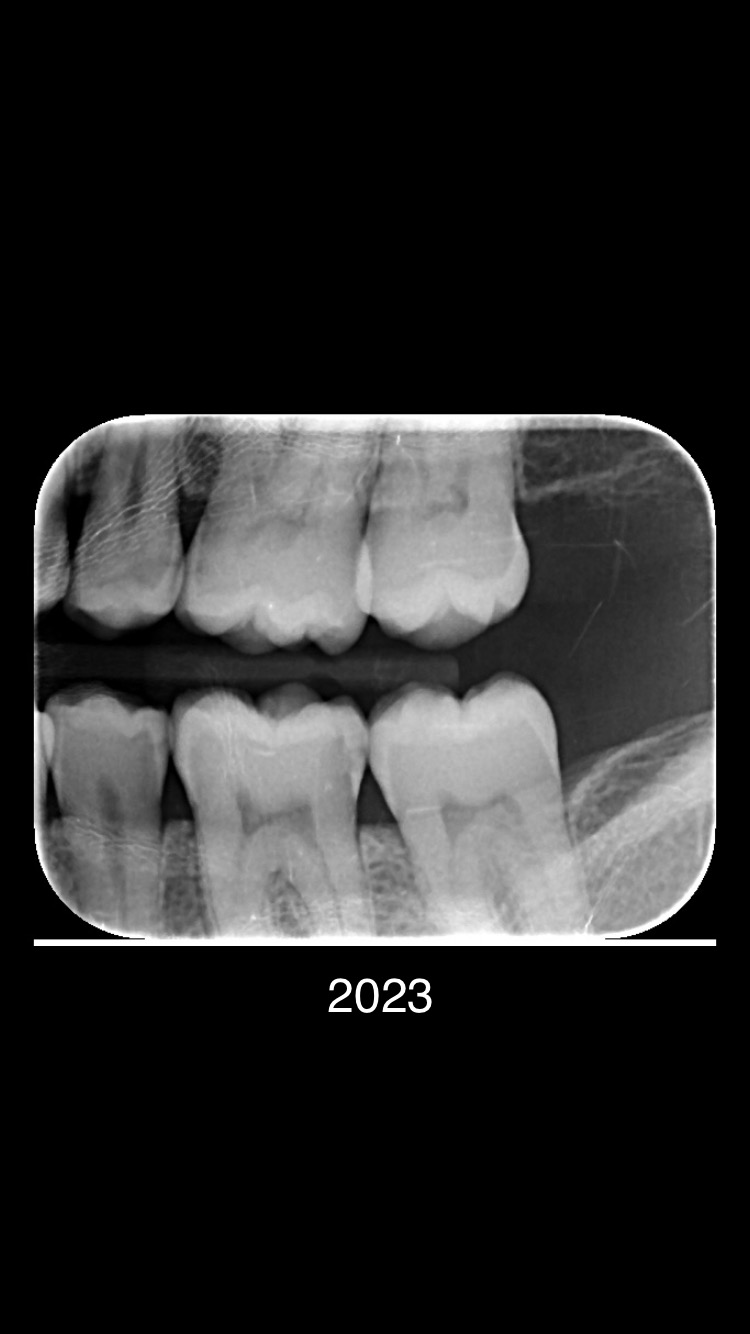

Ik ben heel erg benieuwd of er sprake is van gaatjes in dit gebit. Tot en met 2021 waren er geen gaatjes geconstateerd. Ivm gestopte tandarts (was werkzaam als zelfstandige tandarts praktijk) en praktijk overname spreekt de nieuwe tandarts (werkzaam in een tandartsenpraktijk met meerdere tandartsen) van ruim 7 gaatjes. Kunt u aangeven of dit klopt?

Er zijn meerdere beginnende plekjes maar die zijn nog niet door het glazuur dus hoeven nog niet aangepakt te worden. De vier in de linker boven en onderkaak gevonden "gaatjes" zou ik ook aanpakken. 25.26.35,36.......24 kan ik niet goed beoordelen dus twijfel.16 zou ik nog niet doen. In 2021 waren er links enige die net wel of net niet door het glazuur zijn.. dus ik kan begrijpen dat uw tandarts dat in de gaten heeft gehouden, gemonitord. Maar wat heeft u gedaan tussen 2020/2021 en 2023.. Gebruikt u wel ragers elke dag???>of andere reiniging hulpmiddelen voor tussen de tanden en kiezen. Let op uw voeding/drank gebruik... beperk het aantal invloed momenten op uw gebit tot 6. etc etc. dit gaat fout. Op de status praesens v uw gebit zie ik maar 5 aantekeningen niet 7. Maar ik ben niet goed in rekenen.

Bedankt voor uw reactie. Ik heb in de afgelopen dagen 2 tandartsenpraktijken bezocht, de eerste gaf aan dat er 5 gaatjes zijn. De tweede tandarts vertelde dat er 3 gaatjes zijn, ze noemde 25, 26 en 36. Verder noemde ze vier opkomende gaatjes. Maar ik weet niet waar precies.

Tandarts, als ik het goed begrijp bedoeld u dat u ook ziet dat ik gaatjes heb? Ik heb tot vorige week begrepen dat m’n voormalige tandarts zei dat ik geen gaatjes zou hebben. Links onder heb ik de afgelopen 2 jaar op en af wel een kloppend gevoel gehad, maar m’n tandarts gaf aan dat ik een mondbitje moest dragen bij slapen.

Begrijp ik dat uw advies is dat ik vier tanden de linker boven en onderkaak 25.26.35,36 nu het beste kan laten vullen?

Ik vroeg me ook af of u verstandig vind dat ik nummer 35 en 16 moet laten vullen?